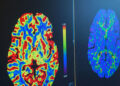

Interventional Radiology is a subspecialty of radiology that is offered at Roane Medical Center in which minimally invasive procedures are performed using image guidance. The concept behind IR is to diagnose or treat pathology with the most minimally invasive techniques possible. IR procedures can reduce infection rates, recovery times, and shorten hospital stays. As a result, many IR procedures are performed with conscious sedation, and the global interventional radiology market is poised for significant growth, all of which are available at RMC!